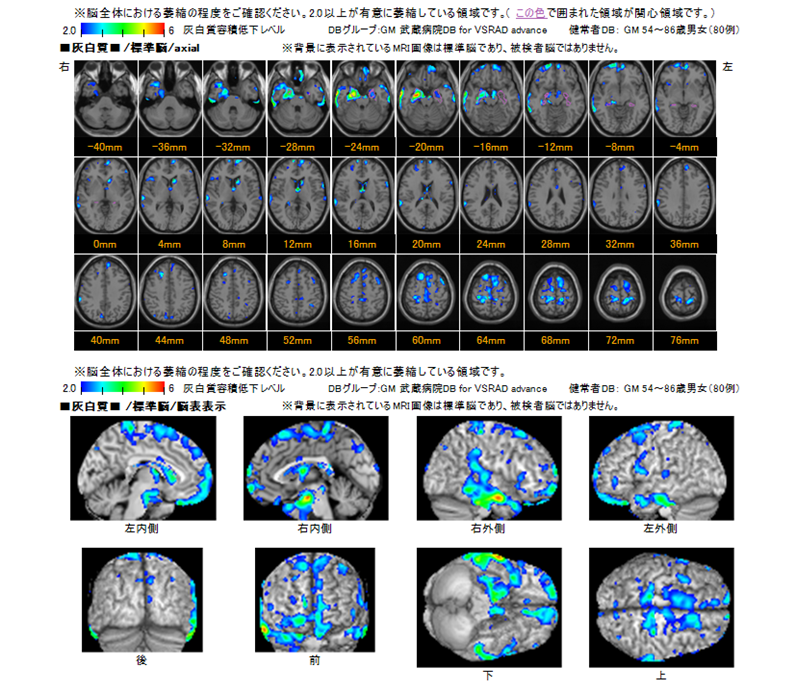

VSRAD(MRI)検査

Voxel-based Specific Regional analysis system for Alzheimer's Disease の頭文字を取ってVSRAD(ブイエスラド)と呼びます。

アルツハイマー型認知症は物忘れの進行とともに脳の萎縮、特に海馬という記憶に関する部分が委縮します。VSRADはこの委縮の程度を見る検査です。

MRI画像を使って、脳の萎縮度をみる検査【VSRAD】によって、早期アルツハイマー型認知症の支援が可能となりました。アルツハイマー型認知症をMRI画像によって診断できるようになると、早い段階からの積極的な治療の開始へと繋がり、結果としてアルツハイマー型認知症の進行を遅らせることが期待できます。